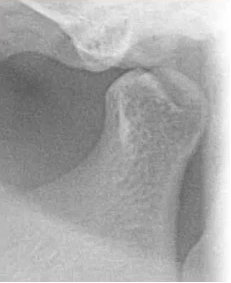

6. 颞下颌关节:髁突外形

比如患者右侧髁突的前斜面发生了硬骨改变。

比如这位患者,当我们在曲面断层片发现有关节髁突的外形改变,就会指引临床大夫做颞下颌关节检查,比如看一下颞下颌关节的张口度、对称性,关节是否有弹响等,必要时需要做颞下颌关节CBCT。

甚至当我们怀疑关节盘有问题时,还需要让患者做磁共振,看下是否有关节盘移位等情况。

颞下颌关节的检查